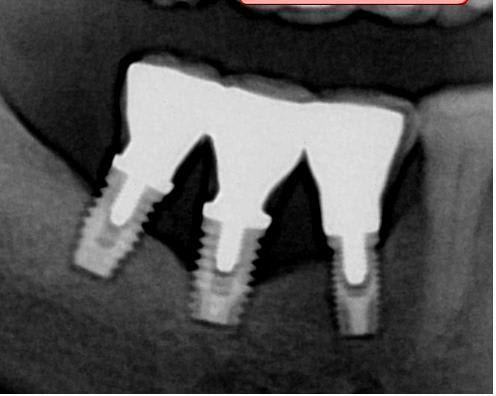

Imp c1ffpg - Eugenol

avec la radio dans ce post, je vois tout de suite 3 échecs dans de l'os qyu me semble de bonne qualité. Les échecs seronts plus au maxillaire supériwur.